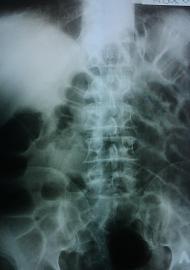

Рентгенологическое исследование брюшной полости является основным инструментальным методом диагностики кишечной непроходимости. Оно основано, главным образом, на факте образования скоплений газа и жидкости в просвете кишечника. При обзорной рентгенографии (-скопии) скопление газа в кишечнике обусловливает появление просветлений на плёнке и на экране, а на фоне их отчётливо видна тень горизонтального уровня жидкости. Скопление газа и жидкости с горизонтальным уровнем, по форме напоминающее опрокинутую чашу ("чаша Клойбера"), являются типичными признаком кишечной непроходимости.

чаши Клойбера

Обзорная рентгенограмма брюшной полости.

Тонкокишечные уровни жидкости - чаши Клойбера (стрелки).

Количество чаш Клойбера широко варьирует. В одном случае наблюдается всего лишь один газовый пузырь с горизонтальным уровнем; в других случаях количество чашек возрастает до 15 и более. Локализуются они в различных отделах брюшной полости, иногда в виде арок: то располагаются в центре брюшной полости, то распределены по её краям; могут находиться на одной линии или полукругом, ступенькообразно или же в несколько этажей. Нижние чашки содержат, как правило, больше жидкости, чем верхние; в верхних жидкость может совсем отсутствовать, и на рентгенограммах в таких случаях видны лишь газовые просветления. Размер чаш Клойбера весьма разнообразен и колеблется от мелких, величиной с напёрсток, до обширных, занимающих почти весь поперечник брюшной полости.

Помимо чаш Клойбера при кишечной непроходимости наблюдается вздутие отдельных петель кишечника газами, которые образуют дугу, направленную выпуклостью вверх, а в их нижних отделах иногда выступают горизонтальные уровни жидкости. Стенки таких "вздыбленных" петель нередко имеют перистый или ребристый рисунок вследствие наличия поперечных линий затемнения, обусловленных утолщёнными циркулярно расположенными складками слизистой оболочки тонкой кишки (складками Керкринга).